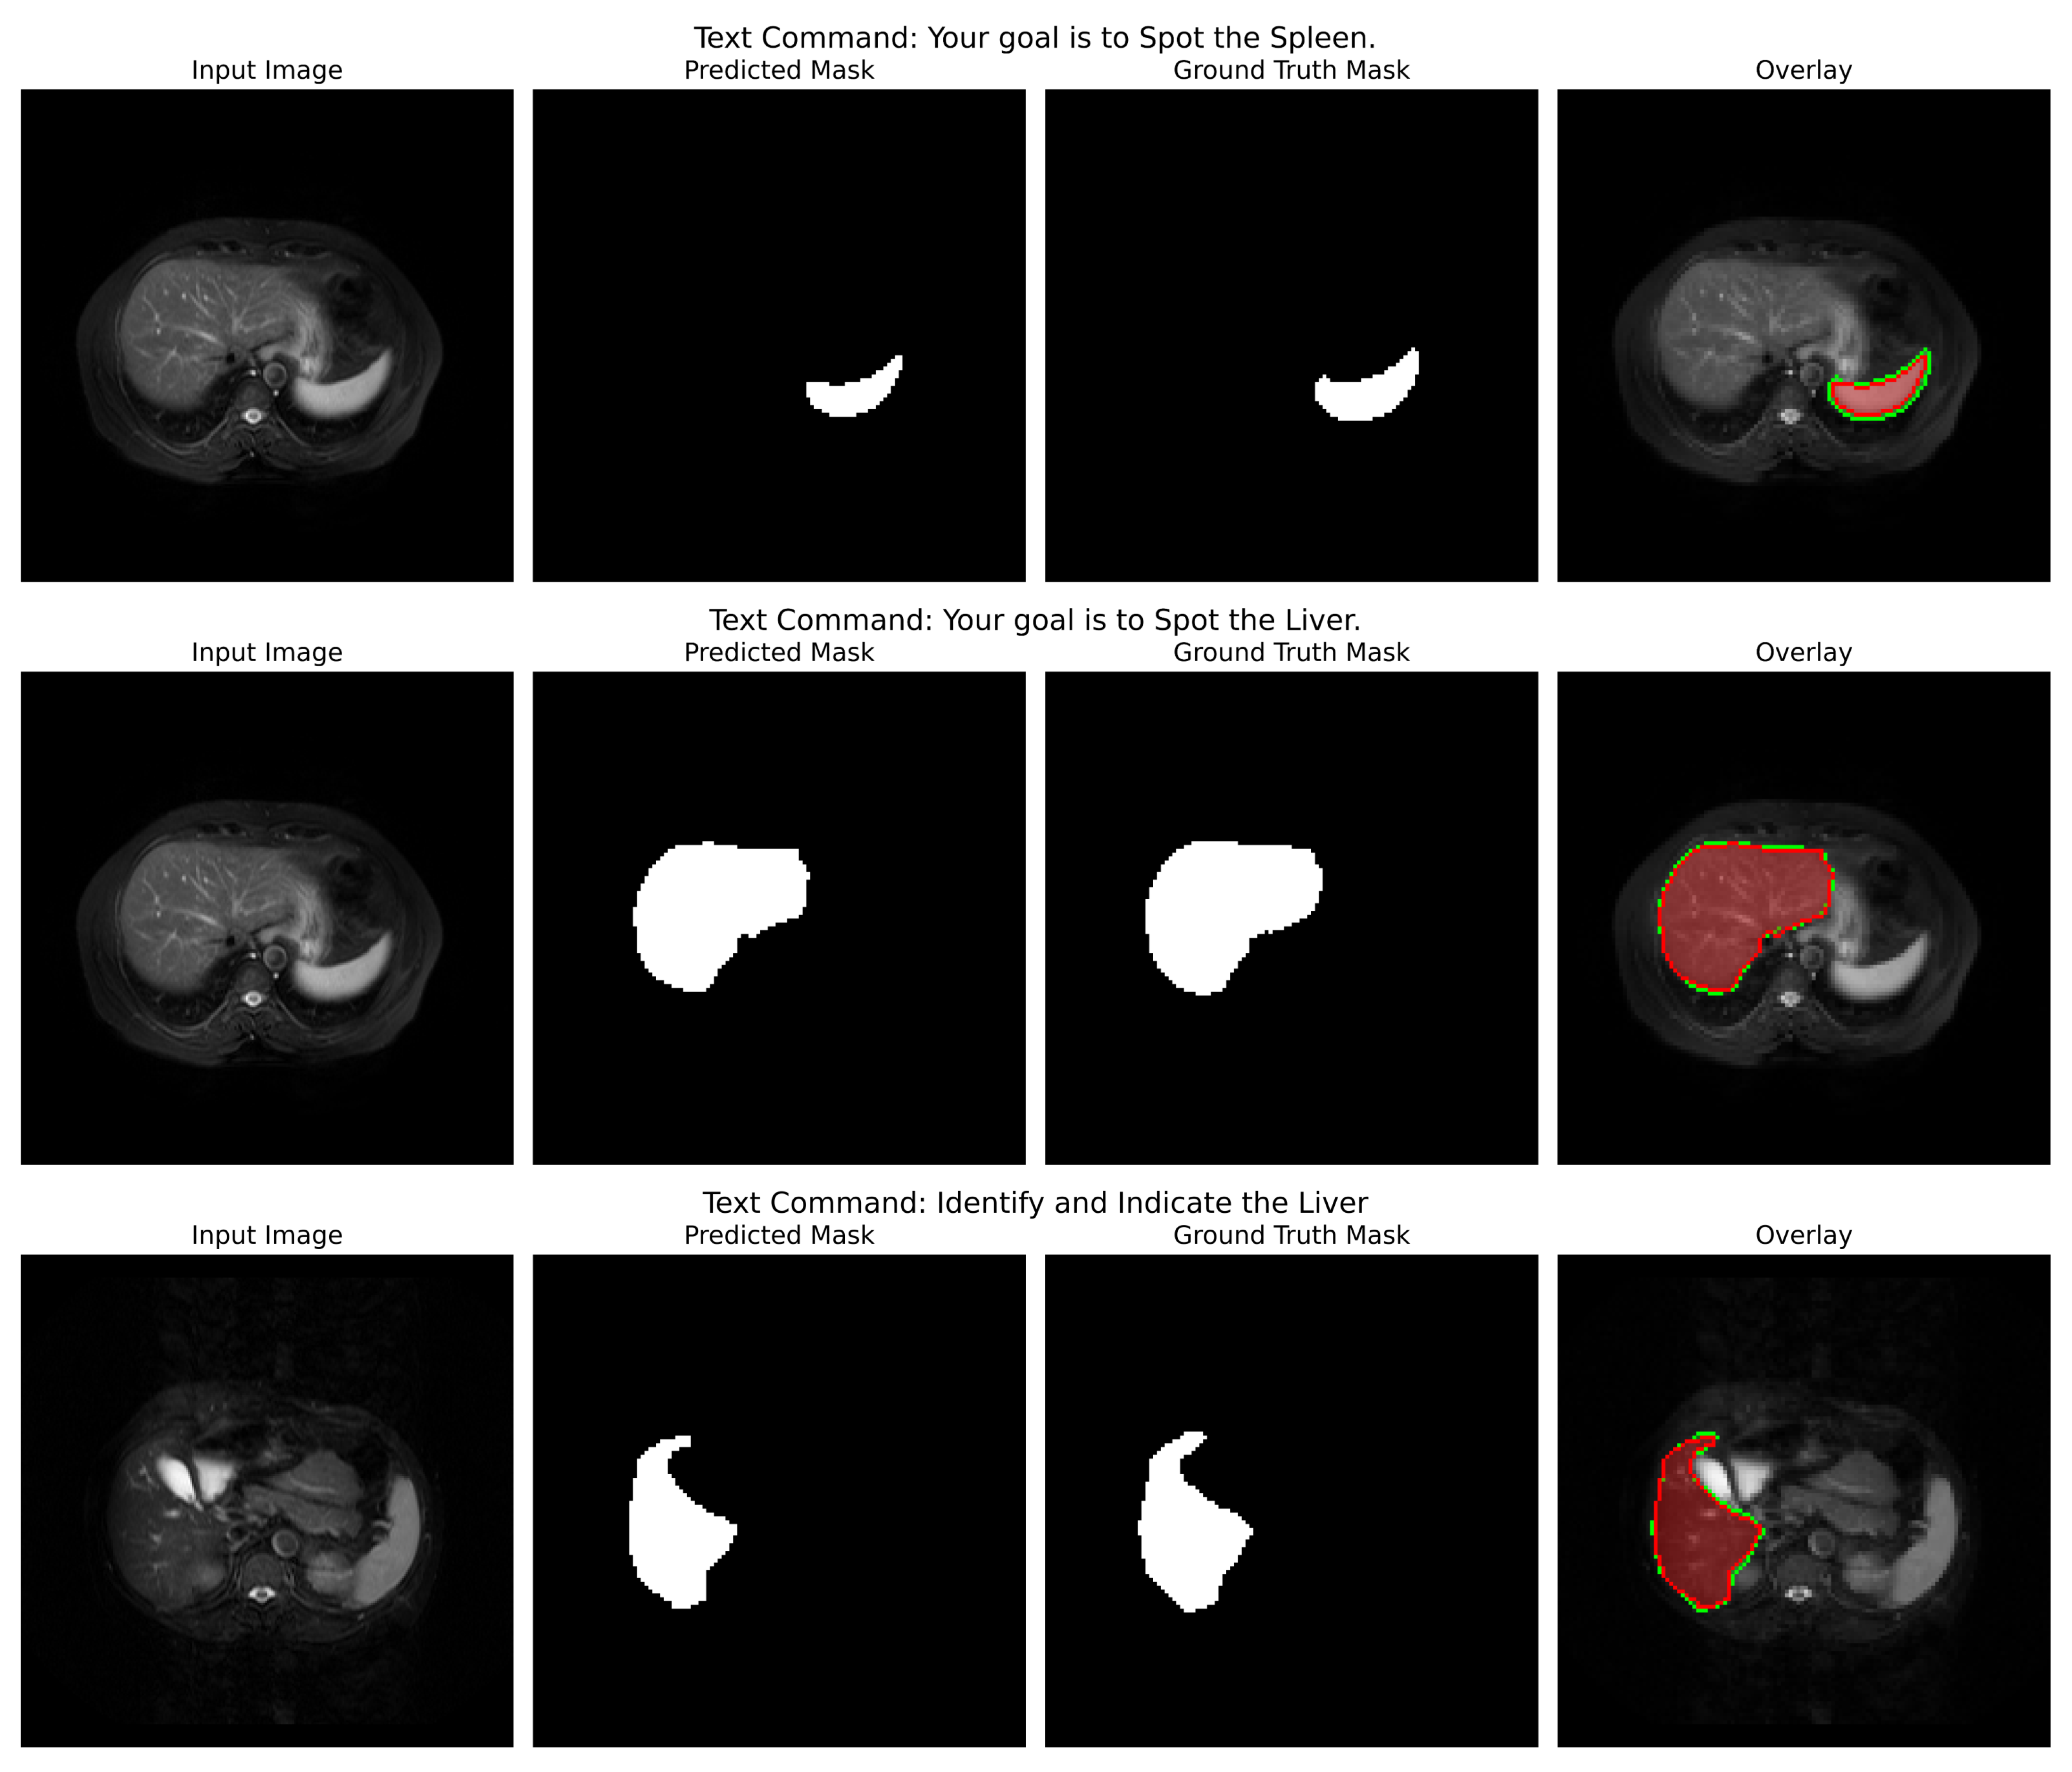

Qualitative Analysis: The analysis is powerfully validated by qualitative outcomes in Figure 7. For Jaccard loss, the sample inference shows an obvious, accurate, and coherent liver segmentation, with sharp boundaries defined along the contours of the organ. The overlay does show a near-perfect match with the ground truth; this is evidence of the generalization ability across the T1-DUAL and T2-SPIR sequences. Such qualitative findings substantiate the quantitative ones: Jaccard loss produces both statistically superior segmentation regarding robustness and consistency and is anatomically faithful.

Insights: An important finding is that the Jaccard loss actually thrives in this extended multi-organ scenario where Dice loss fails to converge. The Jaccard loss could offer a more stable and reliable objective function for the complex multi-organ segmentation since it directs the optimization toward Intersection over Union. Instead, with that consideration, the method identifies balanced solutions that describe each organ’s true shape and size without being misled by the complexity of interactions among multiple structures, thereby making it a preferred approach for this clinically relevant task. This is not just a finding; it is an insight in context that posits the appropriate loss function is not universal but should be chosen based on differing demands imposed by the segmentation task.